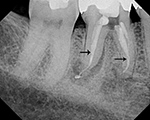

| E - enamel; D - dentine; P - root pulp; R - tooth root; arrows - lamina dura |